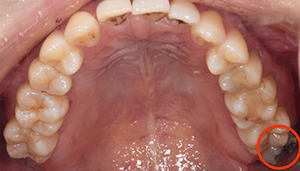

口腔内

- Before

- After

半埋伏の親知らずでした。3糸縫合しました。

CTで親知らずと神経(下歯槽管)の位置を確認しました。

親知らずと神経は一定の距離があり、麻痺などのリスクがほとんどないと判断できます。